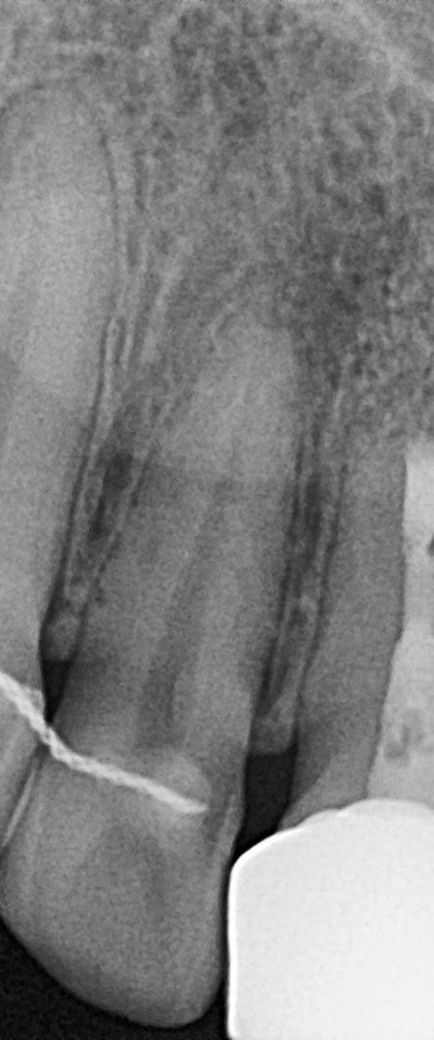

치과에서 파노라마 , 치근단사진 , 씨티 를 함께 찍었고

앞니 뿌리끝 염증이 의심되어 씨티 확인해보니

염증은 없다는 소견을 받았습니다

치과에서는 까맣게 보이는게 뼈의 밀도 차이라고 하셨는데.. 왜 코밑을 누르면 소름돋는 느낌이 나는걸까요 ..

• 1번 째 사진

사진상 보이는 건 lateral fossa입니다 구글에 검색해보시면 연관된 사진 많이 나옵니다 특별히 치아에 큰 문제는 없어보입니다

다만 이제 교정을 한 치아라 뿌리가 좀 짧아져 있는 것도 있고 앞으로 외흡수가 진행될 수 있는 가능성이 있으니 증상이 악화되는지 한번 지켜봐야겠습니다